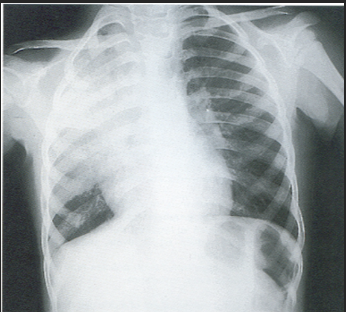

A 3-year-old child is admitted to the hospital due to decreased appetite and weight loss. She has been afebrile, and has not had vomiting or diarrhea.

Her activity level has decreased over the past two weeks.

She had been healthy until 2 months ago, when she was hospitalized for 48 ...

infection with mild respiratory distress and poor fluid intake.